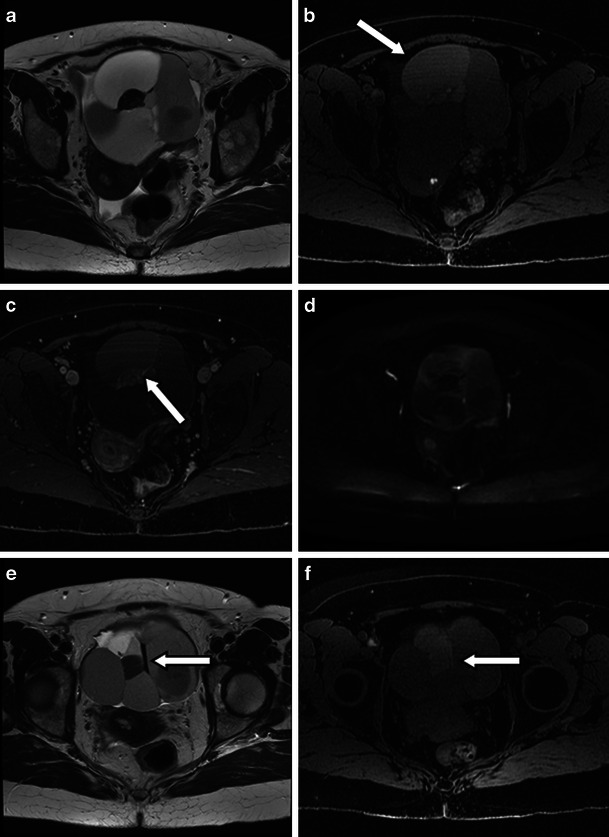

Struma ovarii is a rare type of mature teratoma, but its imaging features are rather distinct. Whilst immature teratomas are known to be predominantly solid with small foci of fat, mature cystic teratomas or dermoid cysts are known to be predominantly cystic, present as a fat-containing mass and are often associated with calcifications as well as an enhancing nodule-forming soft-tissue component [3]. Diagnosis of uncomplicated teratomas using computed tomography (CT) and magnetic resonance (MR) imaging is fairly straightforward because both techniques are highly sensitive in the detection of fat within the tumour, presenting as negative attenuation on CT [7]. On MRI, three methods have been used to distinguish the fatty contents of the mature cystic teratoma from those of endometriomas or other haemorrhagic cysts. First, chemical shift artefact in the frequency encoding direction can be used to detect fat and to distinguish fat from haemorrhage [18]. Second, gradient-echo imaging, using an echo time in which fat and water are in opposed phases, can demonstrate fat–water interfaces and mixtures of fat and water [19]. Third, sequences with frequency-selective fat saturation will suppress the high signal of the intralesional fat in teratomas and help distinguish them from haemorrhagic lesions [3]. MR imaging with this latter technique allows accurate differentiation between teratomas and haemorrhagic cysts and is preferable to the other techniques [3]. The key features of a mature teratoma using water-only and fat-only T1 technique and diffusion-weighted imaging are demonstrated in Fig. 1. Of note is the restricted diffusion present in the sebaceous material within the cyst (Fig. 1).

Fig. 1.

Three-tesla MR images of a mature teratoma or dermoid cyst arising from the left ovary in a 53-year-old patient. The fatty component in the lesion is hyperintense on the 3D-LAVA fat-only T1-weighted image (a) and hypointense on the water-only T1-weighted image (b) (arrows). c T2-weighted high-resolution image shows the fatty component within the lesion to be hyperintense (arrow). The nidus itself contains a fatty component that is also hyperintense on 3D-LAVA fat-only T1-weighted image (a) and hypointense on the water-only T1-weighted image (b) (arrowheads). d Diffusion-weighted image using a b value of 1,200 s/mm2 shows a high signal intensity rim representing restricted diffusion from sebaceous material surrounding the nidus and punctuate areas of restricted diffusion scattered throughout the nidus (arrowhead). The pedunculated uterine fibroid (T) at the level of the right lateral aspect of the uterus presents with typical hypointensity on T2 (c) without associated restricted diffusion (d)